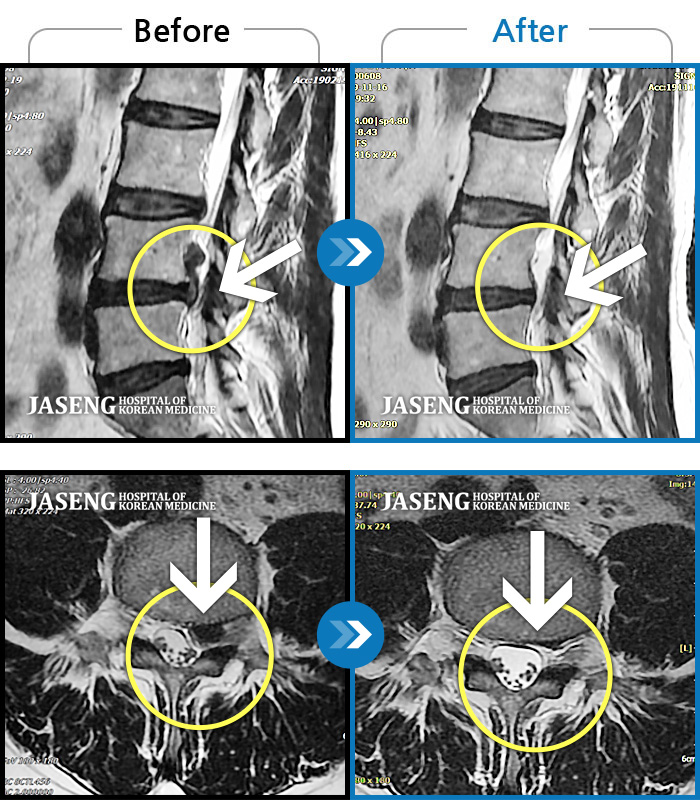

MRI 치료사례

좌측 허리와 골반 통증, 좌측 다리에 통증과 저림